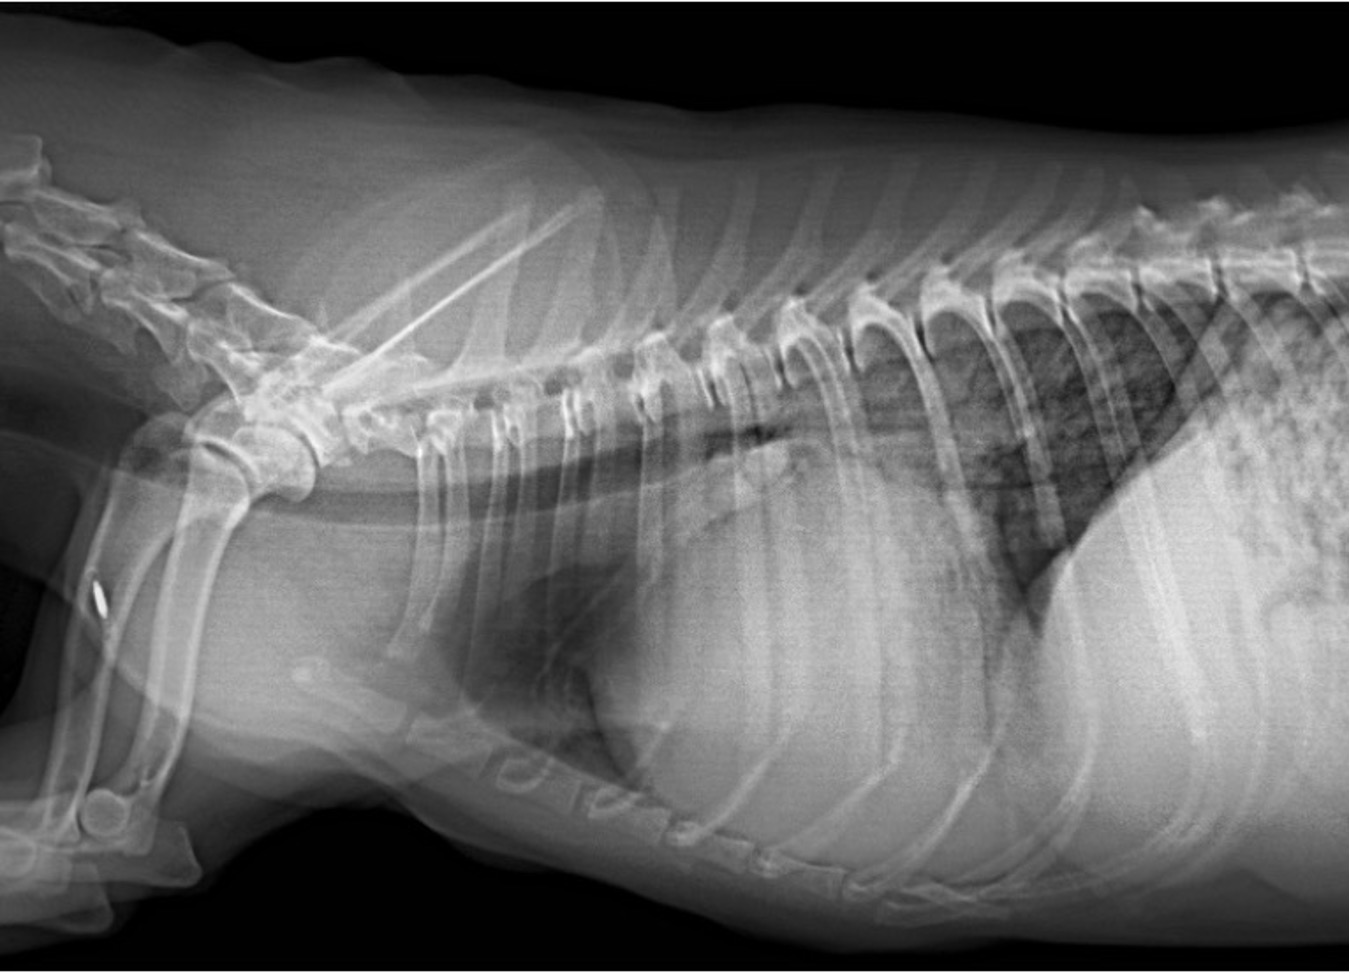

La radiografía de tórax y el TAC, ¿Cómo sacarles el mejor partido?

¿Y cómo la evaluamos en la clínica?

Se evalúa principalmente con ecocardiografía:

Flujo transmitral (Doppler pulsado): relación E/A, tiempo de desaceleración.

Haz clic en la imagen para obtener una vista más ampliada

Doppler tisular (TDI): onda e’ (relajación) y E/e’ (estimación de presiones de llenado).

Aurícula izquierda (LA/Ao): refleja cronicidad de la sobrecarga.

Flujo venoso pulmonar (si es posible).

En la disfunción diastólica, el problema está en el llenado ventricular alterado debid

o a rigidez y/o alteraciones estructurales. Y su principal signo clínico es la congestión a nivel pulmonar (si el problema es izquierdo) o abdominal (ascitis) si es del lado derecho.